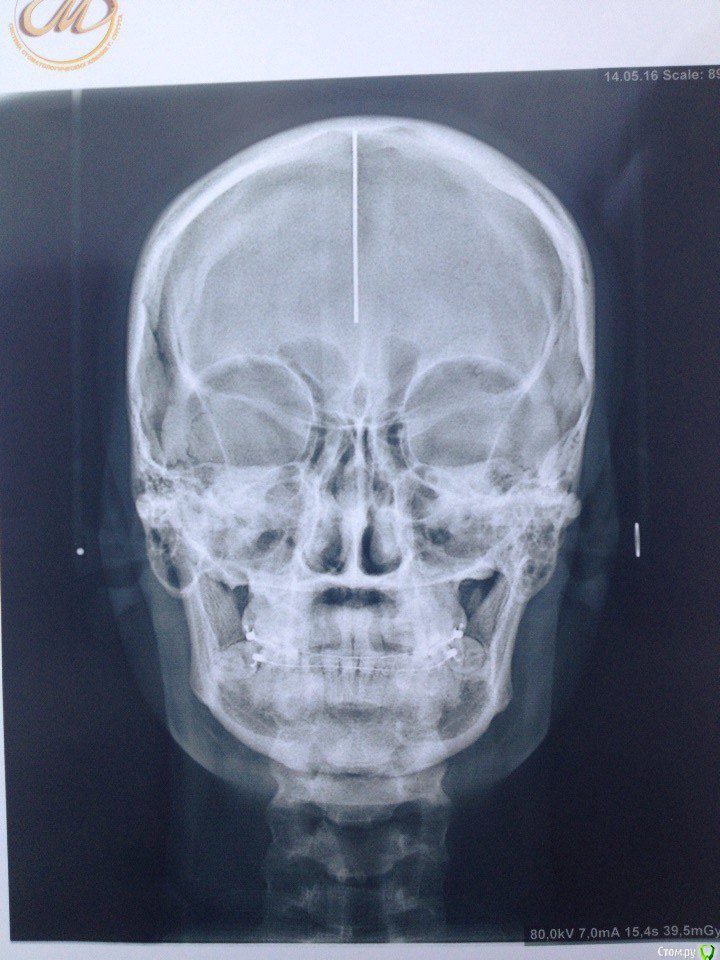

Поставила керамические брекеты в марте 2015 года, ставила для выравнивания зубов (торчали два передних зуба на нижней и на верхней челюсти), проблем с ВНЧС не было, только скрипела во сне зубами, муж неоднократно замечал. На первичной консультации отртодонта предупредила о бруксизме, сказал все нормально, все подобные проблемы именно брекетами и лечатся. Перед установкой делали только ОПТГ и фотографии. Прикус был немного глубокий, как я сама понимаю, во всяком случае от врачей никогда не слышала, что у меня какой-то неправильный прикус. Через месяц после ношения брекетов перестал открываться рот, просто к вечеру я заметила, что не могу его открыть широко, не влазила даже ложка, на осмотре у ортодонта он немножко подпилил накладки, которые были установлены на 6 зубах на НЧ. Ничего не изменилось, на след.осмотре убрал накладки совсем, рот начал открываться, через щелчок или хруст, но не прямо, для широко открытого рта мне приходится делать движение вправо и только так рот открывается до конца, сильных болей не было и нет, бывает ноет в левой стороне возле уха. через несколько месяцев ношения брекетов начала замечать, что челюсть уходит вправо. Вообще на протяжении всего ношения брекетов испытывала дискомфорт в мышцах, все тянуло, и какие то тяжелые челюсти казались. 15 мая сняли брекеты, сделали слепки для капп, мой ортодонт сказал, что сейчас нужно удалять все оставшиеся 8 и походить к остеопату или мануальщику, если не поможет возвращаться делать аксиографию и ставить другие брекеты, на вопрос чем они отличаются он ответил, что с ними можно зуб наклонять в любом положении, в отличии от этих, т.к. с этими брекетами зубы встают только на 90градусов, после снятия брекетов чувствую себя хуже, боль начала появляться в левом ухе, ужасно все напряжено. В нашем городе гнатологов и подобных специалистов нет, ходила на протяжении года к нескольким ортодонтам на консультацию никакой конкретики, грубо говоря все пожимали плечами, не знаю как быть, какие обследования пройти, не поторопились ли мы снимать брекеты (он настаивал), и к кому обратиться, ваше мнение с чем это связано и как теперь решить проблему?